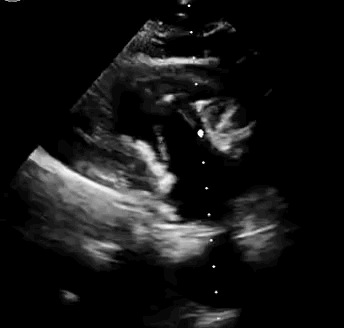

上海中山醫(yī)院葛均波院士、錢菊英院長、周達(dá)新教授、潘文志教授、潘翠珍教授、李偉教授共同完成此次臨床前研究。術(shù)后葛均波院士對Lux-Valve Plus的器械操作性能給予了高度評價,DSA和超聲影像也顯示出在本次研究中Lux-Valve Plus的安全性和有效性俱佳。

本次臨床前研究經(jīng)右側(cè)頸靜脈置入LuX-Valve Plus輸送系統(tǒng)可調(diào)彎鞘管,在DSA及超聲引導(dǎo)下將人工三尖瓣瓣膜植入到原有三尖瓣位置,利用獨特的錨定技術(shù)將人工瓣膜支架可靠固定在預(yù)定的位置。